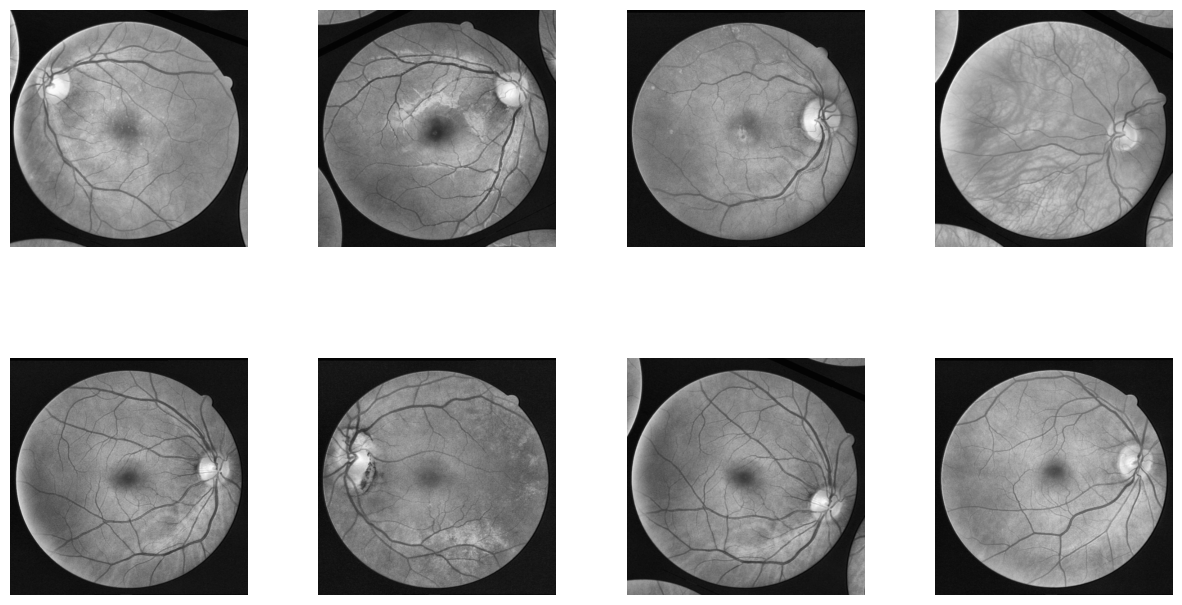

To understand the visual quality and consistency of the annotations, we randomly selected a subset of image-mask pairs from the dataset. These samples highlight the complexity and variability of retinal vasculature, as well as the accuracy and granularity of the manual annotations. The masks clearly delineate the vessel structures, which will be the target for our UNET segmentation model (Fig. 1).

Figure 7 demonstrates a random sample of augmented images from the new dataset.